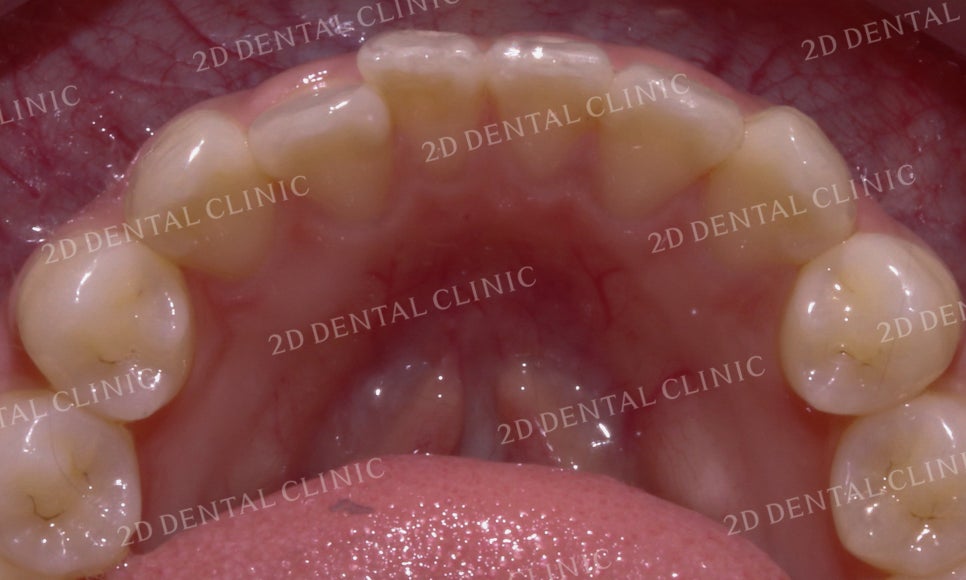

상악의 설측면 사진을 보시면

전치부 치열이 미세하게

들쭉날쭉한 모습이네요.

상악 설측면의 모습을 보면

교정 전후 삐뚤거리던 전치부 치열이

가지런하게 배열된 모습을 볼 수 있습니다.

또한 눈에 띄게 튀어나와 있던

중절치가 돌출감 없이 잘 마무리된 모습이네요!